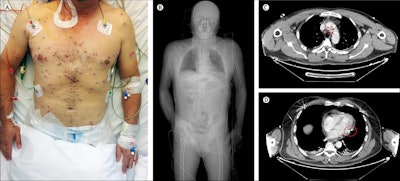

The man underwent a whole-body CT, which showed shotgun pellets distributed throughout his body, some of which had penetrated internally to affect several organs. A chest CT showed that two of the pellets had reached the mediastinum, with one stopping only a few millimeters from the floor of the aortic arch and the other penetrating the pericardium.

A CT angiogram showed no contrast agent leakage from the aorta or pericardium, which led the team to conclude that there was no reason for the patient to undergo cardiac surgery to remove the pellets. After a few days of observation and a course of antibiotics, he was discharged.